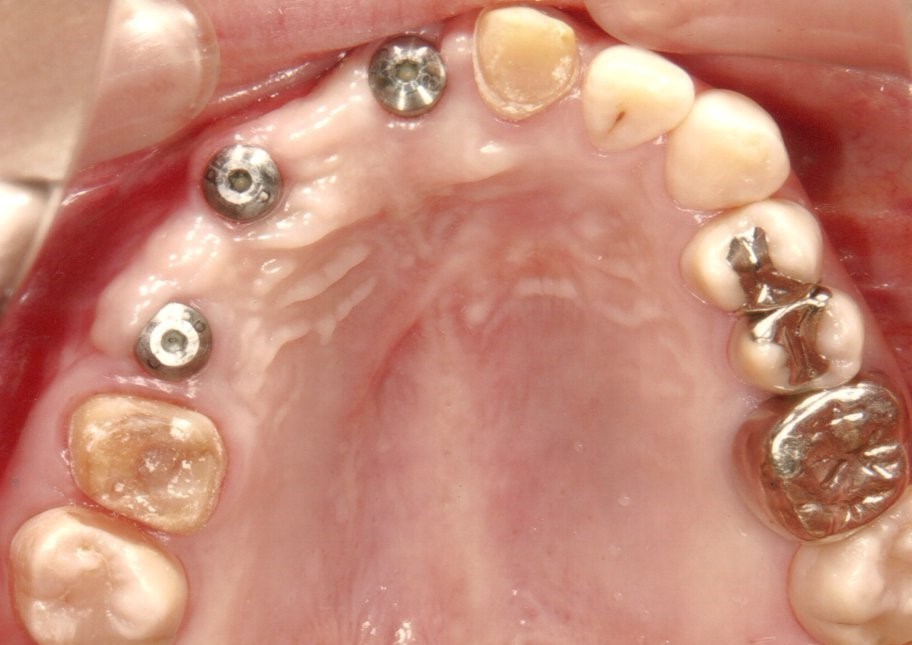

歯周病とインプラント(抜歯即時荷重)<ガイドシステムを使用した埋入法>

インプラント8本で14本の歯を並べたケース・仮歯代含む (函南町在住 女性

抜歯後、片顎8本のインプラントを埋入し、即日に仮歯を製作する事により、1日で片顎14本の歯を回復します。事前にインプラントを埋入する位置をCTによりシミュレーションし、埋入ガイド、仮歯を準備したうえで手術を行います。埋入ガイドにより、正確な位置にインプラントを埋入することができます。

治療の流れ

治療前

下の歯は歯周病でグラグラです。

後のインプラント手術時に、抜歯します。

仮歯装着①

インプラント埋入後、その日に用意していた仮歯を装着します。

仮歯装着②

仮歯をネジ止めして固定します。

これはまだネジ穴を塞いでいない状態です。